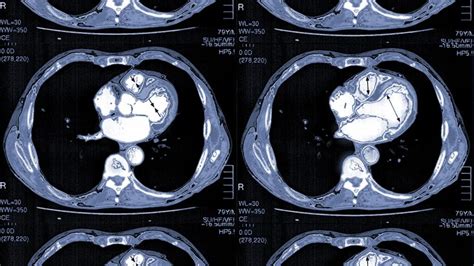

How is a heart ct scan doneA CT scan uses X-rays of the heart to produce detailed images of the heart and the heart arteries, which the doctor can then see on a computer screen.